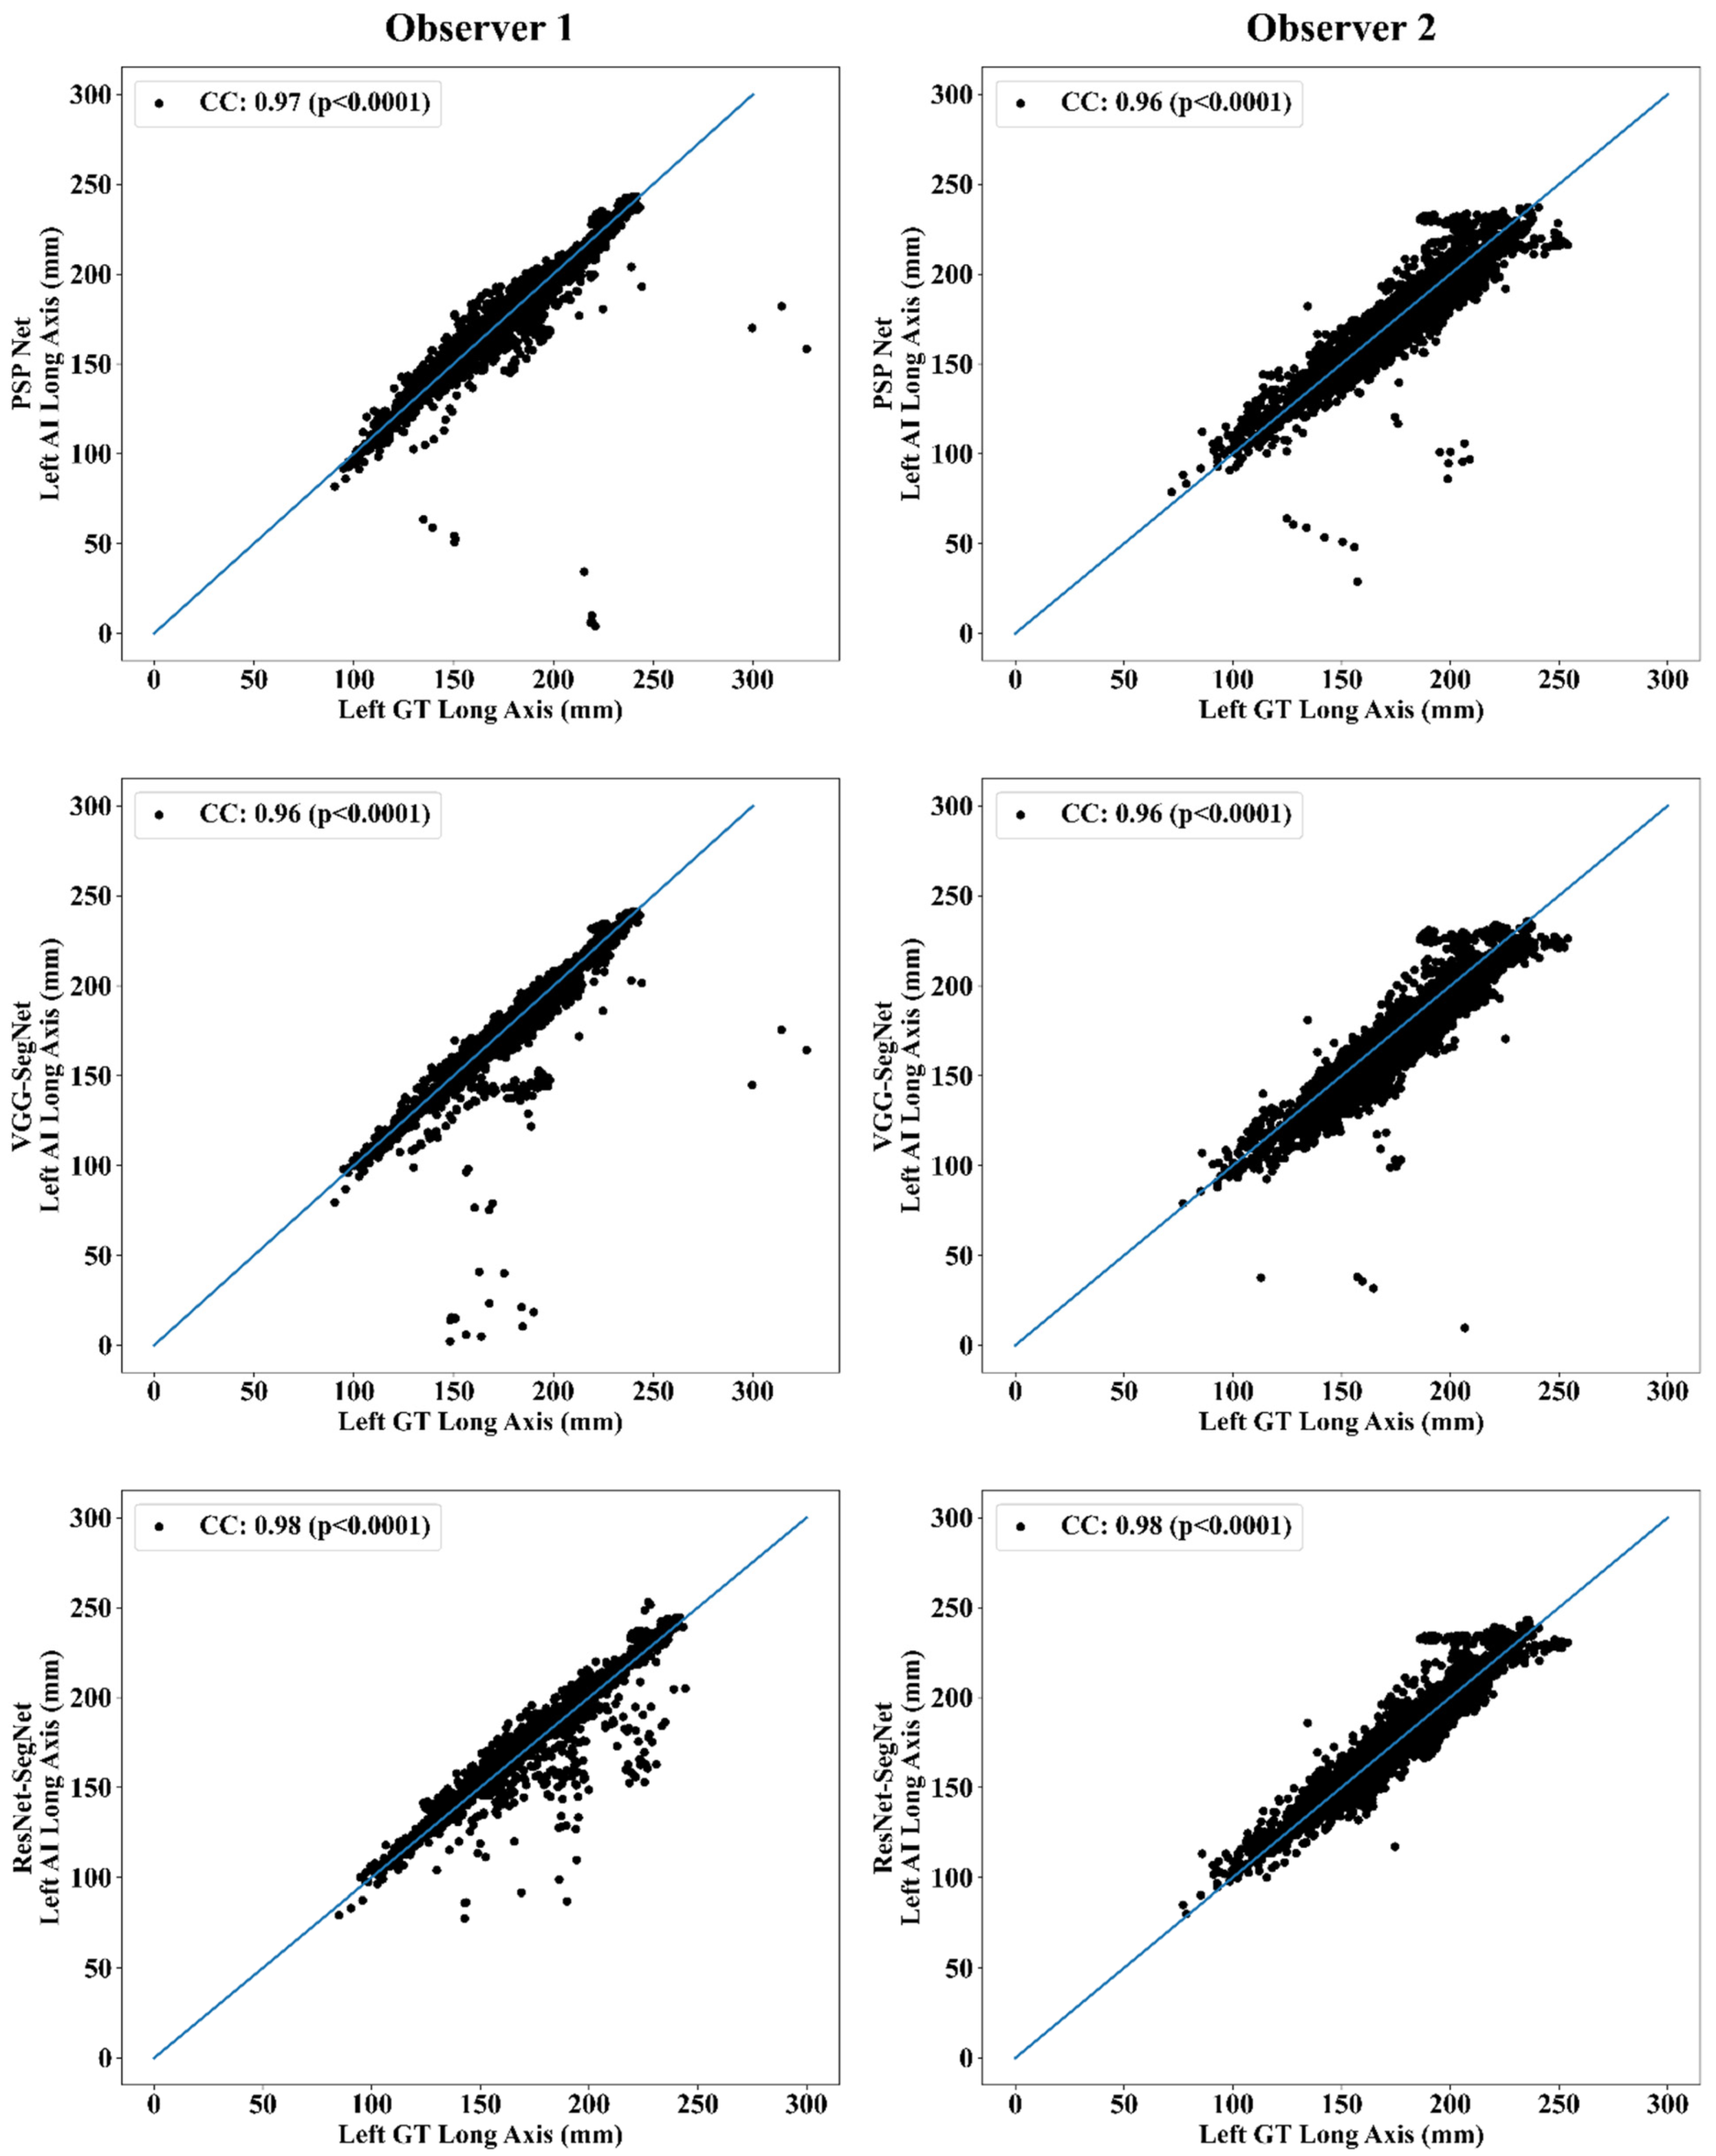

Correlation Plot for Lung Long Axis Error

Statistical Tests